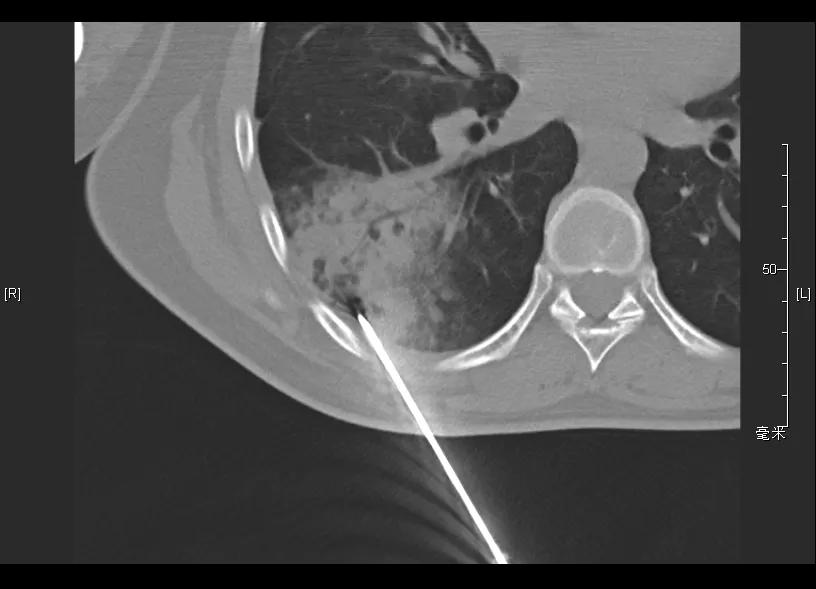

CT引导下肺穿刺活检(2019-05-14)

病理: (肺穿刺)少量支气管壁及肺组织,肺泡间隔明显增宽,可见浆细胞及淋巴细胞浸润,考虑炎症性病变。补充报告:(肺穿刺)特染未提示有血管炎病变。免疫组化:CD31(+),CD34(+)。特殊染色:弹力(-),Masson(-)。

CT引导下肺穿刺活检(2019-08-20)

病理报告: (经皮CT引导右下肺斑片造穿刺活检)少量肺组织,肺泡间隔增宽,部分区域可见类上皮细胞巢和淋巴细胞浸润。免疫组化示肉芽性病变,伴肺泡上皮增生和T淋巴细胞浸润,特殊染色见抗酸阳性杆菌。免疫组化:CD68{KP1}(示组织细胞丰富),CK{pan}(上皮+),Ki-67(25%阳性),LCA(淋巴细胞+),CK7(上皮+),CD3(较多淋巴细胞+),CD20(少数淋巴细胞+)。特殊染色:PAS(-),抗酸(+),六胺银(-),网染(网状纤维+)。

再次调整治疗方案

开始予四联抗结核:异烟肼0.3g qd po,利福平0.45g qd po,乙胺丁醇0.75g qd po,吡嗪酰胺0.5g tid po

停用硫唑嘌呤;糖皮质激素逐步减量至停用。